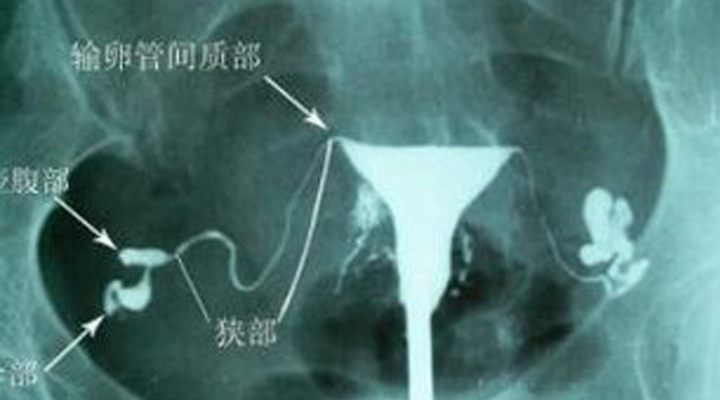

子宮子宮輸卵管造影(HSG)是一種經(jīng)子宮頸管和宮腔進(jìn)行插管和注藥的檢查方法,主要用于了解宮頸管、宮腔和輸卵管的通暢情況,是一種初步評(píng)子宮估輸卵管通暢度的檢查方法,也是不孕癥患者最基礎(chǔ)、最常規(guī)的檢查方法。檢查時(shí)需將導(dǎo)管插入宮腔,因而有因?qū)m頸瘢痕、粘連過緊導(dǎo)致檢查失敗的可能,也由于該項(xiàng)檢查的局限性,有因輸卵管痙攣造成輸卵管不通的假象的可能。